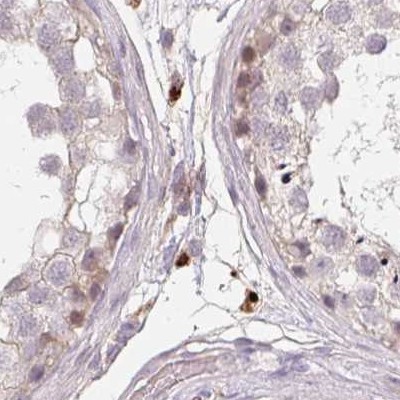

Immunohistochemical staining of human colon, fallopian tube, liver and testis using Anti-TMEM237 antibody HPA052596 (A) shows similar protein distribution across tissues to independent antibody HPA054732 (B).